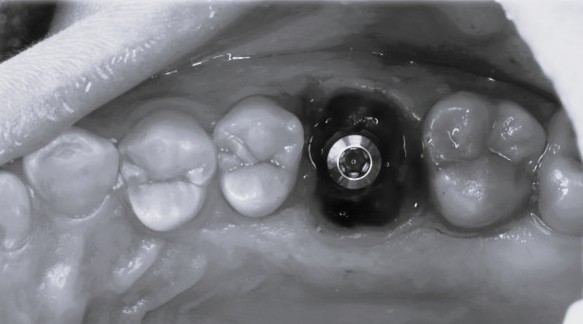

即時埋入での対応

上の奥歯は上顎洞までの距離が短くインプラントが難しいことも多いのですが、即時埋入用に開発されたインプラントを使えば抜歯と同時にインプラント埋め込みまで行うことができると判断しました。

約1時間で抜歯とインプラント埋め込みが終了しました。

条件によっては即時埋入が出来ないことも多くありますが、もし即時埋入が可能であれば術後の痛みや腫れも少なく、短期間で冠をかぶせることが出来ます。

術後も痛みや腫れはあまりなく順調に経過しました。